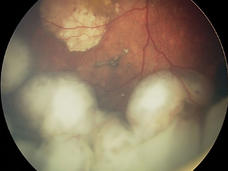

For Childhood Eye Cancer, Researchers Investigating “Packaged” CAR T Cells

For children with the eye cancer retinoblastoma, researchers are studying a CAR T-cell therapy in which the engineered immune cells are packaged in a biodegradable material called a hydrogel and then injected directly into tumors.